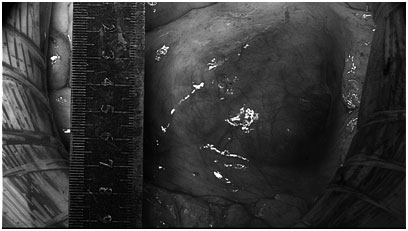

做足了充分的准备,妇科卵巢癌MDT团队于4月25日为张女士施行了手术。术中见腹主动脉右旁一质硬肿物,约6×5×5cm,活动性差,与腹主动脉、下腔静脉、右侧输尿管紧密粘连,累及右侧腰大肌。历经5小时的艰辛,妇科、麻醉科、泌尿外科、肝移植科、手术室等多个学科的通力合作,成功把张女士的血管旁肿瘤完整切除,手术效果评价为R0,基本达到肉眼无残留病灶,没有损伤血管,术中生命体征平稳,术后无需转ICU监护,患者预后好。

手术前病灶,约6*5*5cm